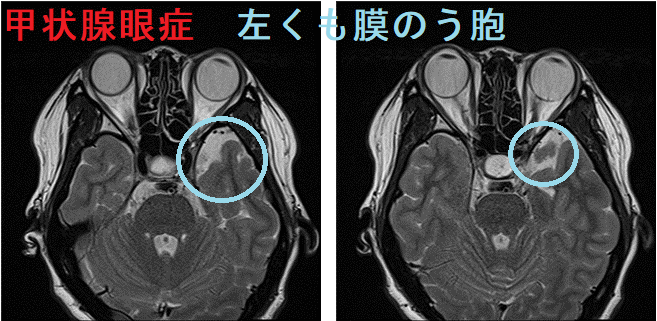

くも膜嚢胞は、くも膜の袋に脳脊髄液が貯留したものです。0.1~0.3%の頻度(1000人~330人に一人)で、男性に多い。

- バセドウ病眼症(甲状腺眼症)の眼窩MRI検査時に、偶然見つかる場合があります